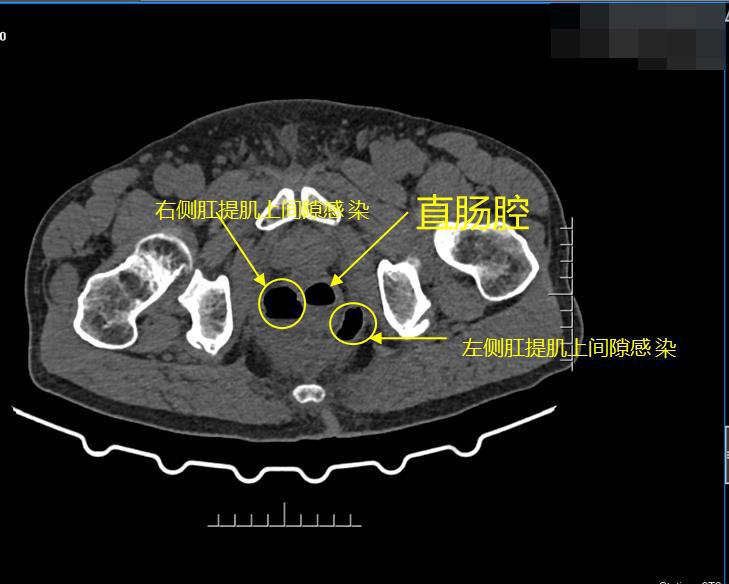

科室门诊医生凭借丰富临床经验果断精准研判病情,肛肠科团队第一时间牵头实施广泛切开引流挂线急诊手术,术中发现患者肛管直肠周围脓肿合并直肠穿孔肛提肌上间隙感染,肛肠科团队凭借高效处置、规范救治,成功阻断感染扩散,化解了危及生命的险情。